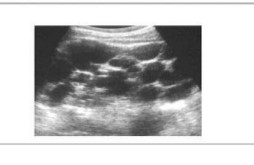

En esta forma de poliquistosis aparecen y se desarrollan quistes en el tejido renal, que progresivamente ocupan el parénquima normal junto con zonas de fibrosis e inflamación intersticial. Es frecuente que se acompañen de quistes en otros órganos o que se asocien anomalías vasculares. Se suele manifestar en la vida adulta, sin embargo excepcionalmente puede tener expresión clínica en el neonato. En general, la probabilidad de hallar quistes renales aumenta con la edad, siendo más frecuente en la tercera década. En la etapa prenatal y neonatal se puede realizar el diagnóstico por ecografía con la aparición de riñones hiperecogéncos con o sin quistes y la afectación bilateral renal quística compatible con la enfermedad en uno de los progenitores.

Si bien es excepcional la manifestación clínica en el neonato, la poliquistosis renal autosómico dominante es un diagnóstico a tener en cuenta en todo recién nacido con riñones agrandados de tamaño sin afectación de la vía urinaria. Es muy importante la evaluación ecográfica renal de ambos padres.

Figura 2.9.5.3. Poliquistosis renal autosómica dominante (2 imágenes)